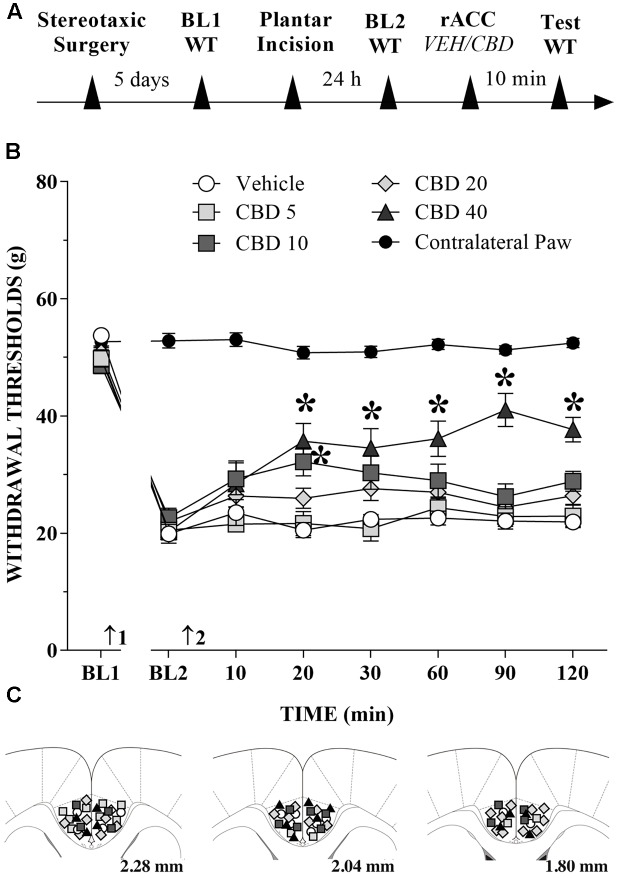

CBD Injection into the rACC Reduces Mechanical Allodynia in Incised Rats

The great majority of injection sites were concentrated in the rACC (2.28 to 1.80 mm in relation to bregma). Representative photomicrograph of injection sites is shown in Figure 4. Time line of the protocol for the experiments is shown in Figure 5A. The local injection of CBD (40 nmol/0.25 μL) produced a reduction of the mechanical allodynia that lasted for at least 120 min. The decrease of mechanical allodynia started 20 min after CBD (10 and 40 nmol/0.25 μL) but was maximal at 90 min after the highest dose, which elicited a significant increase in the force required for paw withdrawal. The differences were statistically significant in terms of time [F(7.476) = 133.4; p < 0.01], treatment [F(5,68) = 134.1; p < 0.01] and interaction time × treatment [F(35,476) = 17.2; p < 0.01]. The threshold of the non-incised hind paw did not change throughout the period of observation (Figure 5B). Figure 5C illustrates the microinjection sites in the rACC on diagrams of cross-sections from the atlas of ref. Paxinos and Watson (2006).